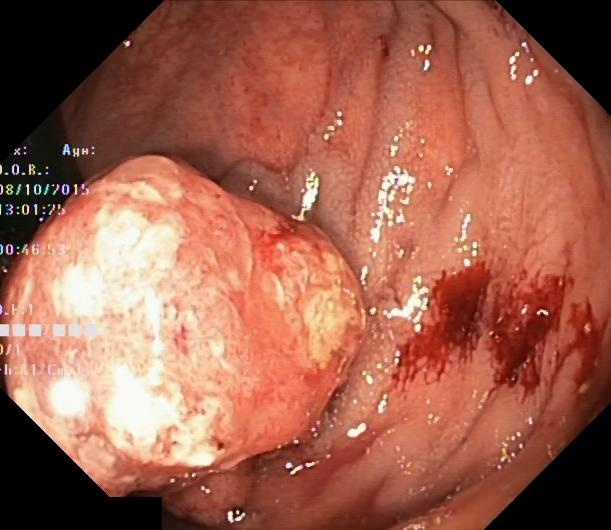

4、Kvasir : 该医学影像数据集是由挪威癌症登记处与挪威放射学协会共同发起开发的。该数据集包含了大量CT扫描图像资料,并旨在促进对肺结节及结肠息肉的自动检测与分割研究。

处理好后的COCO格式的数据集图像的总数为1000张,类型标签为病灶区域。